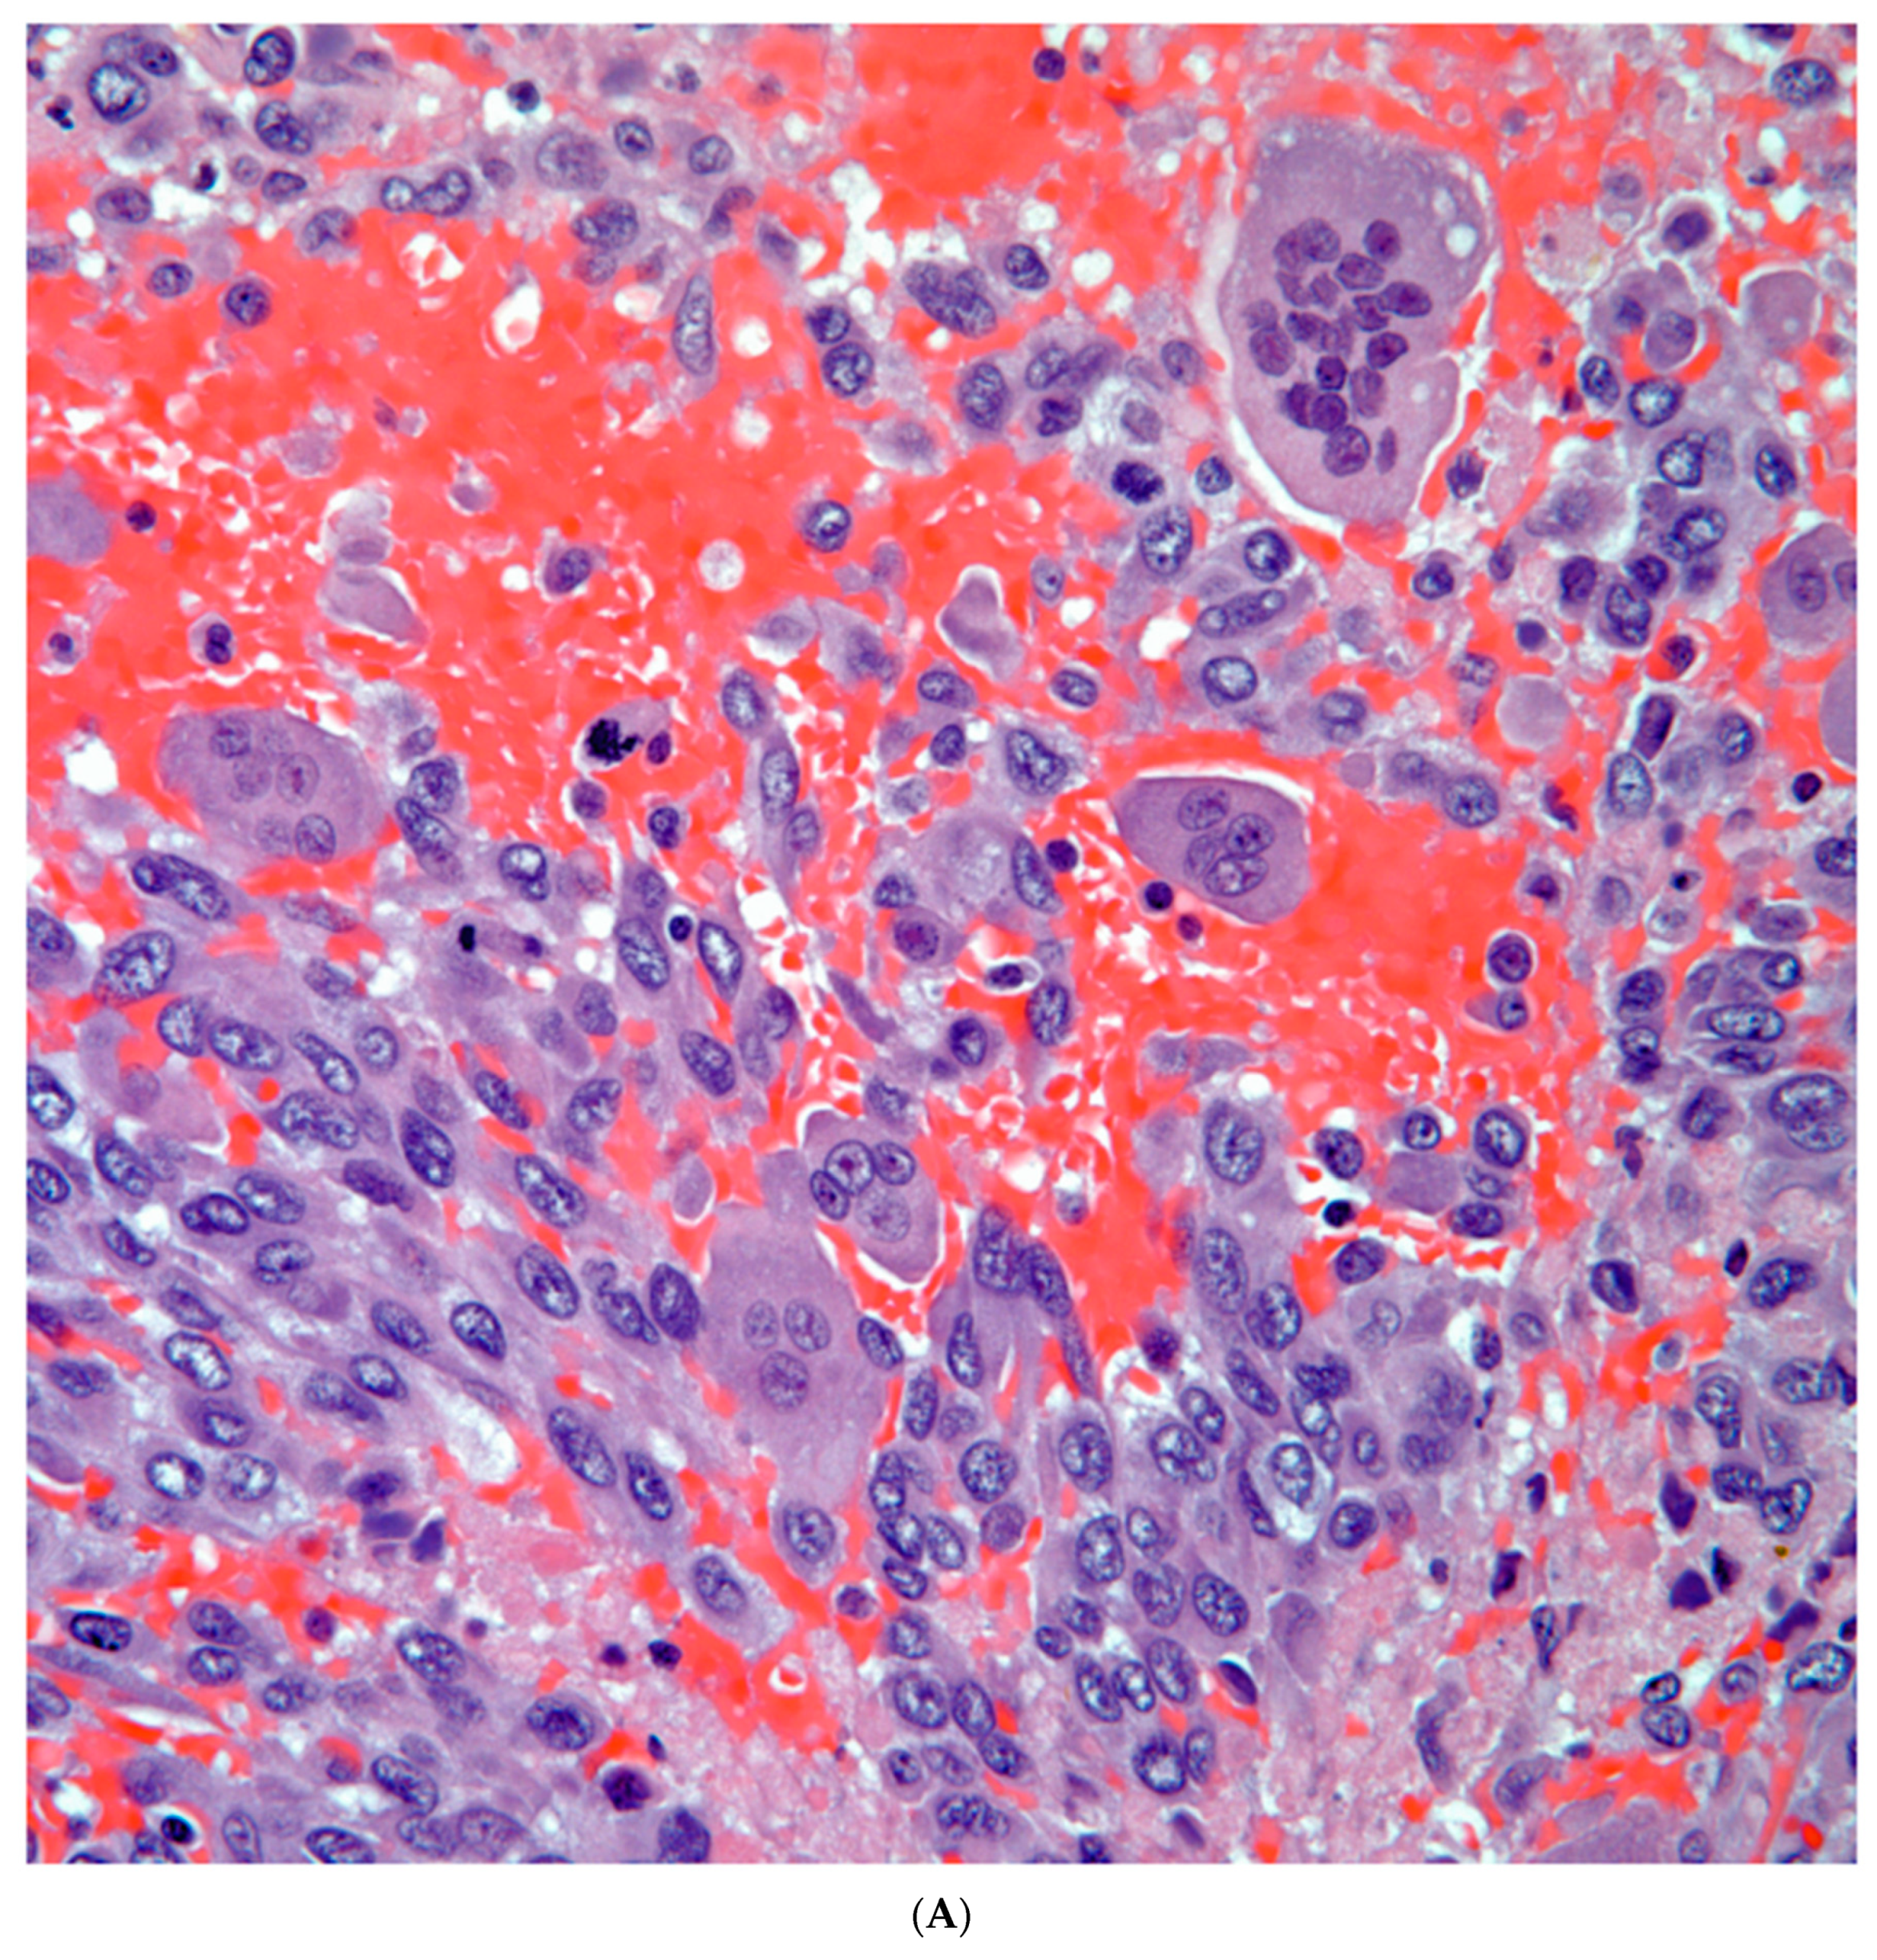

Sarcomatoid carcinomas: these tumors show a tightly packed spindle cell proliferation composed of slender cells with fusiform nuclei and inconspicuous nucleoli, replacing normal lung parenchyma. The tumors are well delimited but not encapsulated (Figure 1). Cellular atypia is variable and may show areas of mild to moderate to marked atypia. Mitotic figures also vary and may be inconspicuous or may be evident with the presence of atypical mitotic figures (Figure 2A,B). In high grade tumors, the presence of necrosis and hemorrhage is prominent and is mixed with the neoplastic component. Important to recognize is that sarcomatoid carcinomas may be associated with areas of otherwise conventional non-small cell carcinoma such as adenocarcinoma or squamous cell carcinoma (Figure 3A,B). In addition, sarcomatoid carcinoma may also show the presence of bizarre giant cells admixed with the spindle cell component (Pleomorphic carcinoma) (Figure 4).

Figure 2. A) Neoplastic spindle cell proliferation; B) Atypia and mitotic activity.